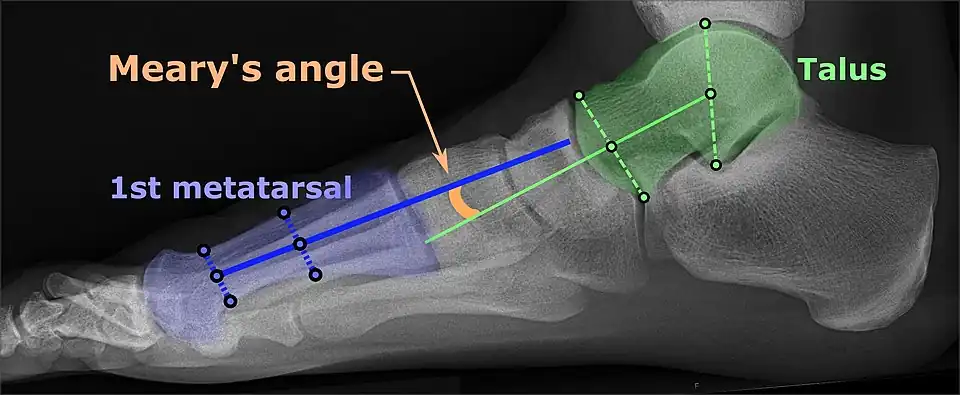

On plain radiography, flat feet can be diagnosed and graded by several measures, the most important in adults being the talonavicular coverage angle, the calcaneal pitch, and the talar-1st metatarsal angle (Meary's angle).[11] The talonavicular coverage angle is abnormally laterally rotated in flat feet.[11] It is normally up to 7 degrees laterally rotated, so a greater rotation indicates flat feet.[11] Radiographies generally need to be taken on weightbearing feet in order to detect misalignment.[12]

Weight-bearing lateral X-ray showing the measurement of calcaneal pitch, which is an angle of the calcaneus and the inferior aspect of the foot, with different sources giving different reference points.[13] A calcaneal pitch of less than 17° or 18° indicates flat feet.[11] -

Same lateral X-ray showing the measurement of Meary's angle, which is the angle between the long axis of the talus and first metatarsal bone.[11] An angle greater than 4° convex downward is considered a flat foot, 15° - 30° moderate flat foot, and greater than 30° severe flat foot.[11]